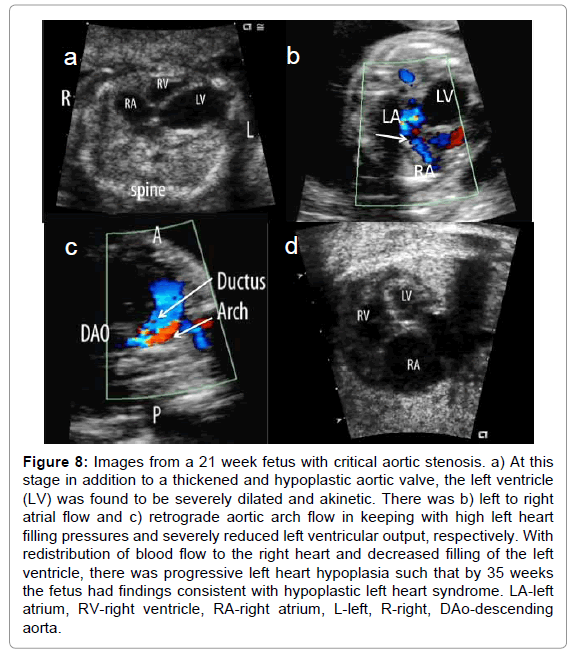

Early in our experience, the cardiac lesions detected before birth represented a worse spectrum than what was generally encountered postnatally; however, increased experience and improved technology have facilitated the detection of less severe disease including minor valve abnormalities, small ventricular septal defects and unilateral or isolated anomalous pulmonary venous connections. Fetal echocardiography has also permitted the detection of unusual cardiovascular pathologies, many of which would not otherwise clinically manifest after birth due to lack of symptoms and others may never be encountered, as they are associated with intrauterine demise. As an example of the former, small ventricular diverticula may be identified through their association with massive pericardial effusions on the fetus [20,21] (Figure 3). The pericardial effusions usually resolve spontaneously, and by birth, the diverticulum is no longer visible. Rarely, however, they may be associated with spontaneous rupture and fetal demise. Abnormalities of the fetal shunts, as well, significantly influence the fetal circulation but after delivery are no longer be clinically apparent. As an example, agenesis of the ductus venosus may be associated with high fetal cardiac output and heart failure [22]. Following delivery at a viable age, the recommended treatment, the high output state is no longer present. Isolated foramen ovale restriction before birth may be associated with a diminutive left ventricle and right ventricular dilation; however, with delivery, this discrepancy resolves [23].

clinical-experimental-cardiology-fetal-echocardiography

Figure 3: LV free wall aneurysm versus diverticulum in a 20 week twin fetus. a) A massive pericardial effusion prompted initial referral for fetal echocardiography. b) On further imaging, a thin outpouching was demonstrated (arrows) arising from the lateral wall of the left ventricle (LV) which communicated through a small neck with the LV cavity. c) During ventricular systole, blood entered this hypokinetic aneurysm (arrow at neck). Spontaneous rupture led to an acute demise of this fetus at 24 weeks. L-left, R-right, LV-left ventricle, LA-left atrium, RV-right ventricle, LVOT-left ventricular outflow tract.